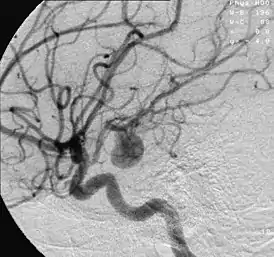

Аневри́зма — выпячивание стенки артерии (реже — вены) вследствие её истончения или растяжения; расширение просвета сосуда более чем в 2 раза. Причиной могут служить врождённые или приобретённые дефекты средней оболочки сосудов. Также термин применяется для обозначения истончения и выпячивания стенки камер сердца (в подавляющем большинстве случаев — левого желудочка). Аневризма сердца является осложнением инфаркта миокарда.

- Ангиография («золотой стандарт» диагностики)